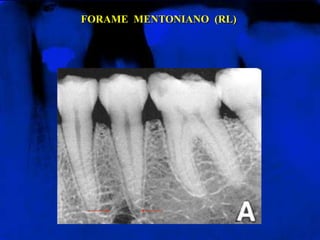

FORAME MENTONIANO (RL)

Área radiolúcida arredondada ou oval, de pequena

extensão, localizado, na maioria dos casos, entre os ápices

dos dois pré-molares

FORAME MENTONIANO (RL) Árearadiolúcida arredondada ou oval, de pequena extensão, localizado, na maioria dos casos, entre os ápices dos dois pré-molares